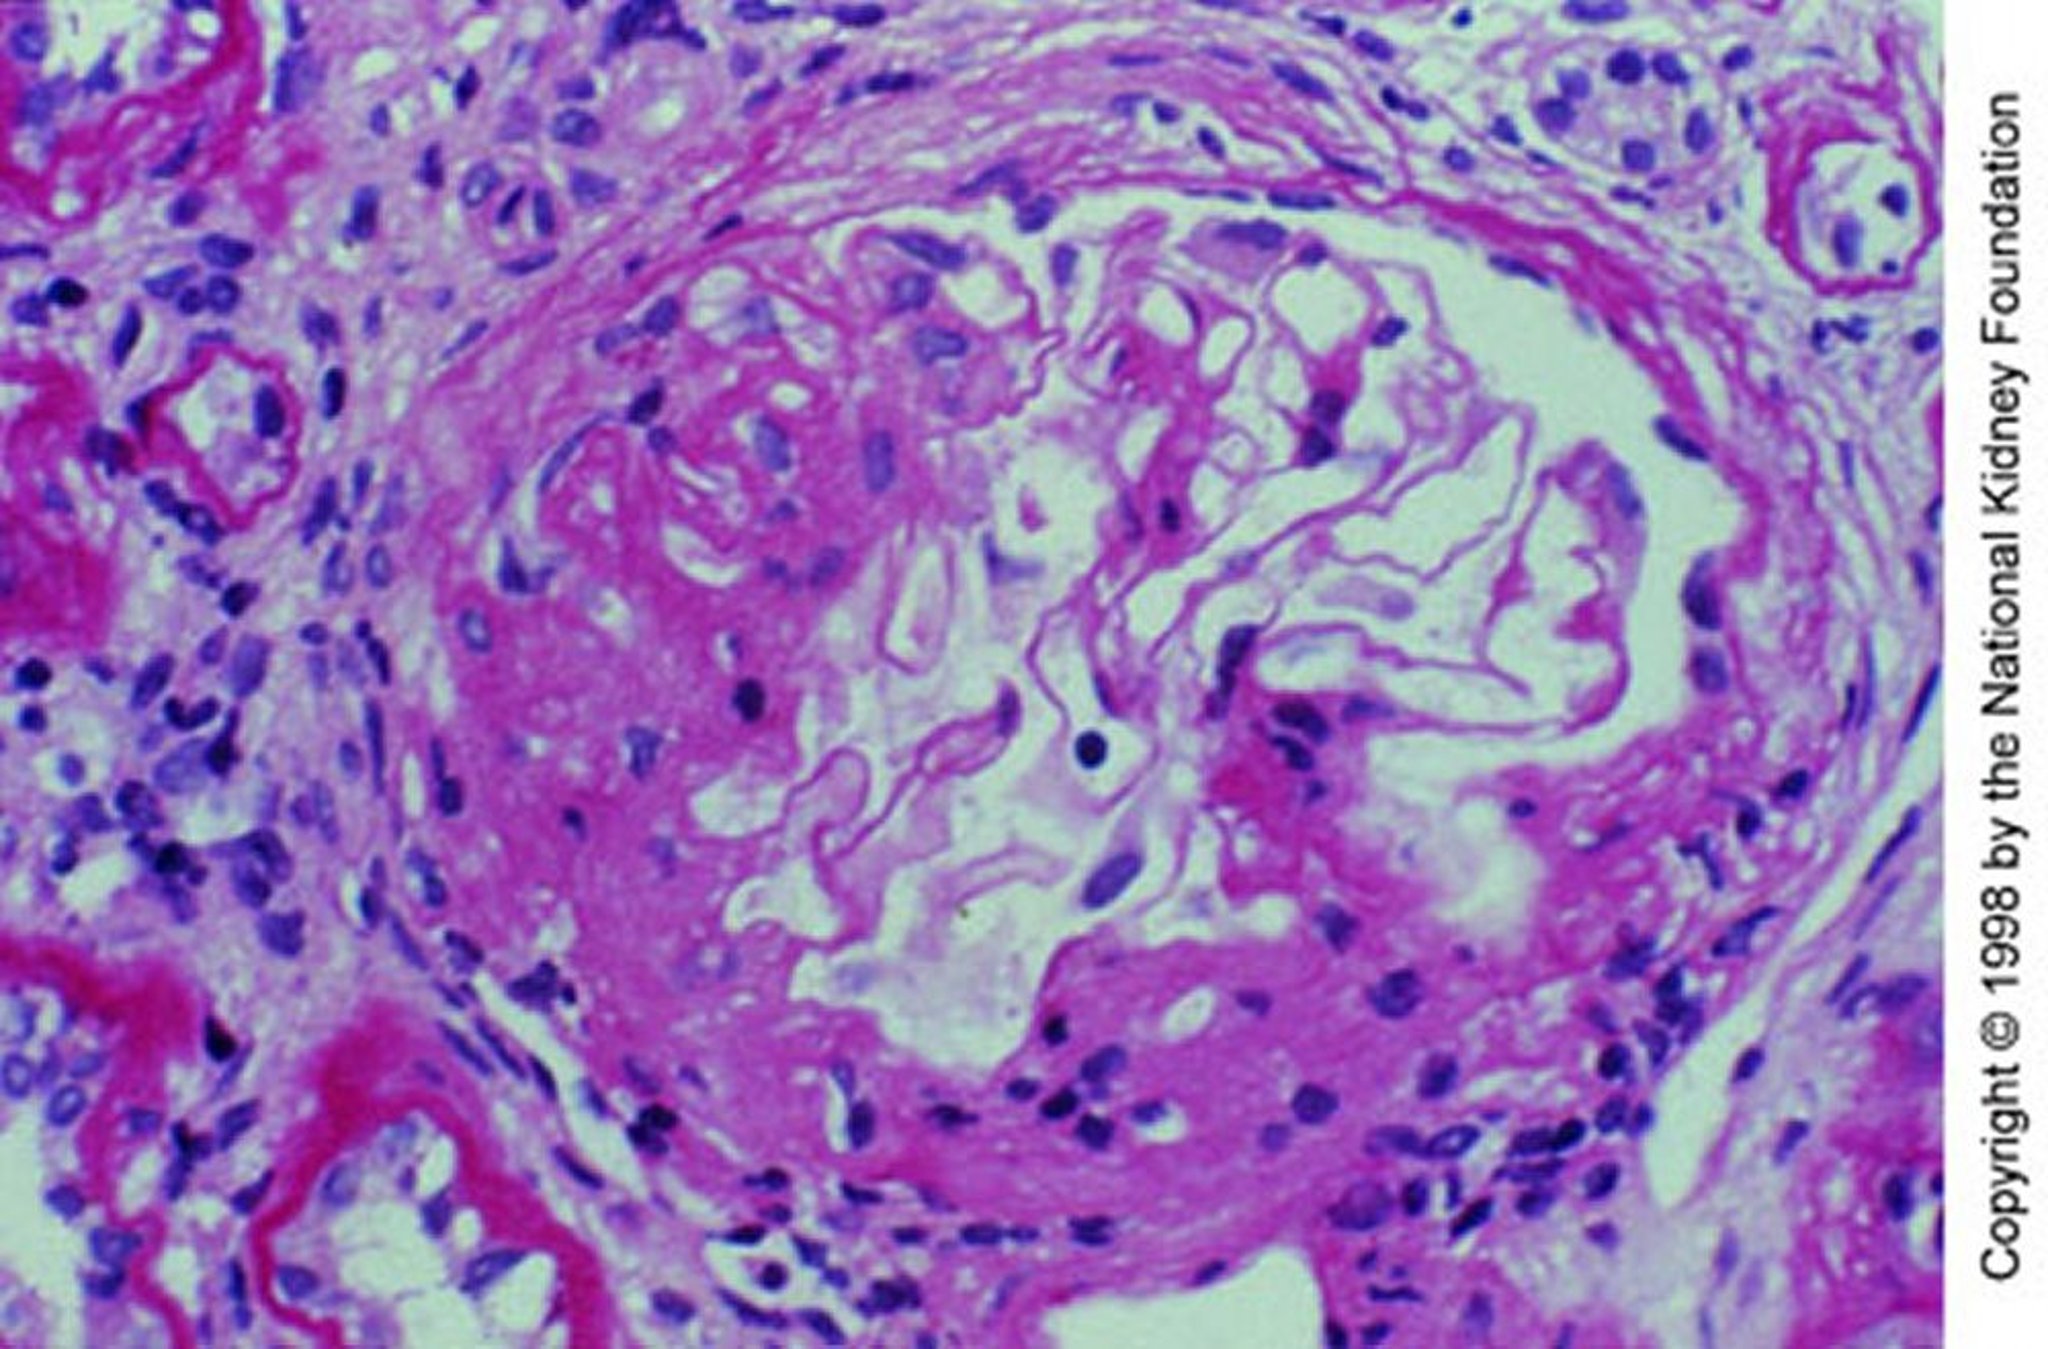

Nefropatia por IgA (expansão mesangial)

Expansão mesangial com esclerose segmentar (coloração com ácido periódico de Schiff, × 200).